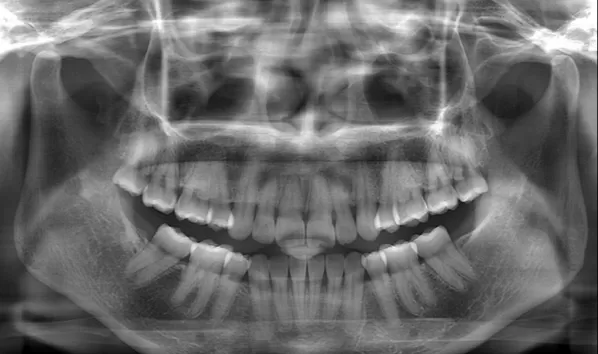

X-rays before treatment

[Panoramic Radiography/Lateral Cephalogram]